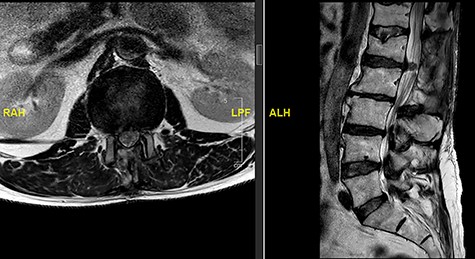

A 56-year-old male patient lumber decompression in a local neurosurgical centre for severe canal stenosis at L1/2 and L2/3 (Fig. 1) level after presenting with bilateral leg weakness and perianal numbness. Three months later he presented with recurrence of right leg pain radiating into the calf and worsening back pain as well as distal lower limbs weakness bilaterally with no sphincter problem. Following an magnetic resonance induction (MRI), which revealed a disc prolapse at L1/2 (Fig. 2), the patient was referred to our Centre. The images were reviewed by a consultant radiologist and as a possibly of intradural herniated disc disease was described. Intraoperatively no extradural disc prolapse was found, so midline durotomy was performed. Intradural disc herniation (IDH) was identified, which was communicating with the disc space through a midline defect in anterior dura (Fig. 3). This was removed extracted under the microscope. Post-operatively, he had a CSF leak needing re-suturing of dura. The patient did make a good post-operative recovery with no major sensory or motor deficits or sphincter disturbance.

Initial MRI images prior to index procedure revealing stenosis at L1/2 and L2/3.